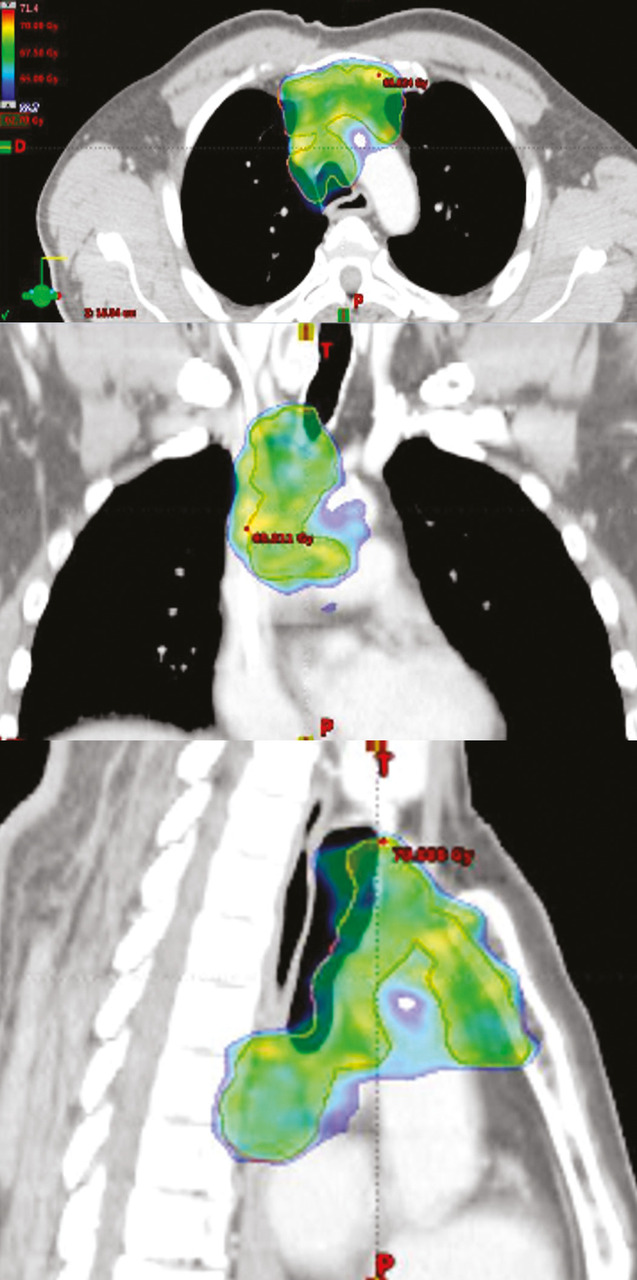

Radiothérapie conformationnelle avec modulation d’intensité

La radiothérapie conformationnelle avec modulation d’intensité (RCMI) – dont il existe plusieurs variantes  : arcthérapie dynamique, tomothérapie – est devenue la technique standard de traitement de la plupart des cancers, notamment en situation curative.14 Elle permet de sculpter la répartition de la dose sur le volume cible (tumeur ou lit tumoral et adénopathies) et ainsi d’épargner les OAR avoisinants (fig. 2). Elle est indissociable d’un contrôle qualité régulier lors du traitement grâce à l’imagerie de contrôle embarquée sur les accélérateurs (imagerie 2D ou 3D scanographique). Si la RCMI est bien sûr utile chez tous les patients, elle prend toute sa place chez la personne âgée, limitant les effets indésirables aigus et tardifs  : diminution très significative de la xérostomie lors des irradiations de la sphère ORL à l’origine de mycoses et de dénutrition d’installation rapide et souvent sévères chez le sujet âgé, diminution de la fréquence et de la sévérité des diarrhées, des rectites et des cystites dans les irradiations abdomino-pelviennes, meilleure protection de la moelle iliaque dans les irradiations pelviennes, ce qui peut être un atout en cas de syndrome myélodysplasique.